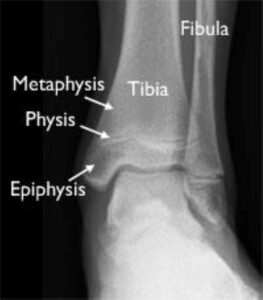

Understanding Ankle Fractures in Children

In children and adolescents, ankle fractures typically affect the tibia or fibula, often involving the growth plates—specialized areas of cartilage near the ends of long bones. Growth plates play a critical role in bone development, gradually hardening into solid bone as the child matures. However, because these growth plates are the last parts of the bones to solidify, they are particularly prone to injury and fractures.